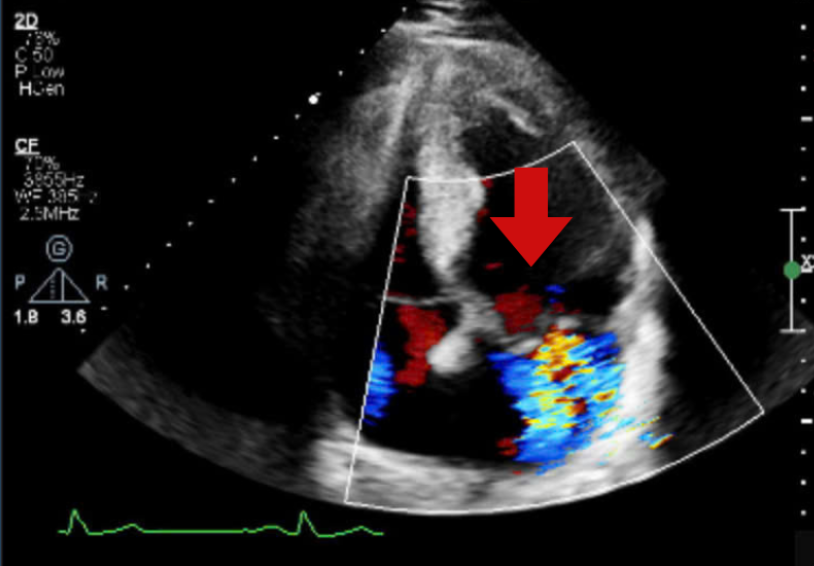

Khi tiến hành siêu âm Doppler tim toàn diện, bác sĩ phát hiện van hai lá bị sa và hở nhiều, khiến máu trào ngược trong tim. Tình trạng này kéo dài đã làm các buồng tim bên trái giãn to, chức năng co bóp của tim bắt đầu suy giảm. Đây là những bất thường khó có thể phát hiện nếu chỉ siêu âm nhanh hoặc đánh giá tổng thể, mà cần khảo sát kỹ từng vùng cơ tim ở nhiều góc độ khác nhau.

Siêu âm tim ghi nhận hình ảnh dòng màu hở van hai lá - Ảnh BVCC